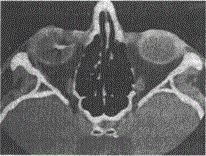

一23岁患者,CT扫描结果如图所示。该患者可诊断为A.左眼玻璃体内异物B.左眼球壁异物C.右眼球壁异物D.右眼玻璃体内异物E.正常眼球结构

选项 A.左眼玻璃体内异物 B.左眼球壁异物 C.右眼球壁异物 D.右眼玻璃体内异物 E.正常眼球结构

答案 D

解析 :图中显示有眼玻璃体内有极高密度阴影,应考虑为球内异物。